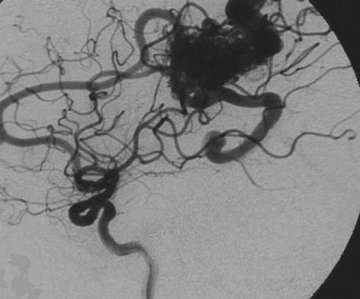

Many patients with AVMs have no symptoms. Some patients may have seizures or persistent headaches related to the AVM. However, most AVMs, as stated above, come to attention due to bleeding. This bleeding in the brain causes a severe headache that is rather sudden in onset and is typically associated with nausea and vomiting. Patients with bleeding in the brain may also lose consciousness. Patient with bleeding is evaluated typically with a CT scan. Once bleeding is confirmed on a CT scan, definitive diagnosis of an AVM is made by angiography. Figure 3 shows the typical appearance of an AVM on angiography. MRI is also very helpful particularly with localizing the AVM. Once the location and appearance of the AVM is decided, definitive plans for treatment are made.

Figure 3. The AVM is seen as a dense collection of vessels (the nidus) that connect the arteries directly to the veins without an intervening capillary system. Next is a picture depicting approximate location of this AVM in the brain. Red arteries bring oxygenated, high pressure blood to the AVM nidus. Blue veins drain blood from the AVM. Arrows indicate direction of the blood flow.

Not all AVMs require embolization. Prior to treatment, there is a discussion between the treating physicians as to whether embolization will be helpful in a particular AVM. Only if deemed useful, is embolization performed (Figures 5. and 6.) It is understood that embolization has its own risks apart and separate from the risks of surgery or radiation. Therefore, if not useful, it is not prudent to expose the patients to the risk of embolization on top of the risk of surgery or radiation.